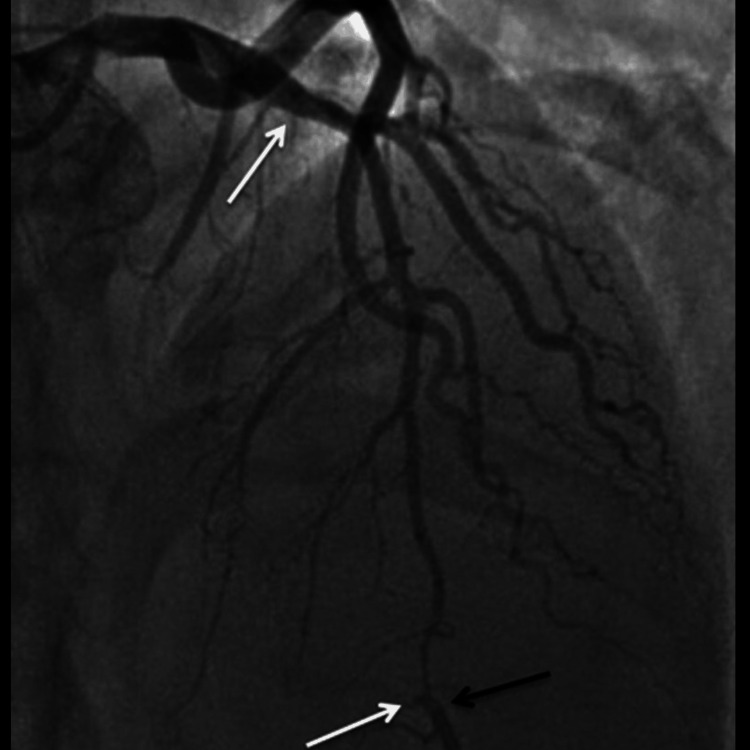

Further diagnostic investigation was pursued through cardiac catheterization, which uncovered a diffuse dissection involving the mid-distal portion of the LAD artery, the posterior descending artery (PDA), the second diagonal branch of the LAD, and the first obtuse marginal branch (OM1) of the left circumflex artery. These findings confirmed the diagnosis of SCAD. The echocardiogram supported these findings showing a left ventricular ejection fraction (LVEF) between 35% and 40% and a fixed mural thrombus on the apical wall of the left ventricle, which are indicators of significant cardiac dysfunction.

The patient’s urine toxicology screen returned positive for Δ9-THC, indicating recent marijuana use, which could have contributed to his cardiovascular event given the known hemodynamic effects of cannabinoids. The angiographic findings illustrating the progression and extent of the coronary artery dissections are sequentially shown in Figures 1–3, providing visual confirmation of the clinical and diagnostic narrative described above.